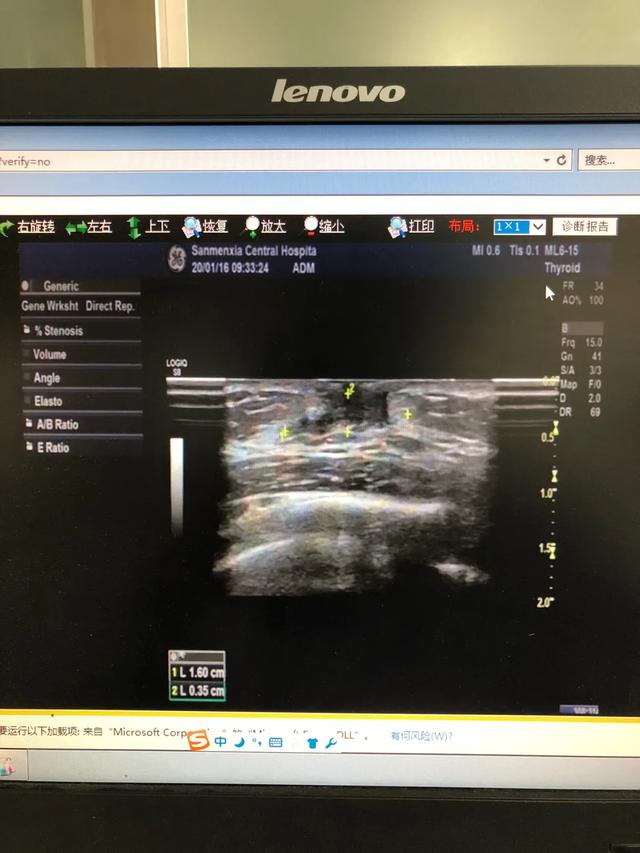

下图是一例患儿性早熟的B超结果、胸片结果及血清学化验结果。

从检查结果来看,B超显示子宫卵巢有囊性回声;胸片显示乳腺发育;而血清学指标,促黄体生成素的峰值是13.09,促卵泡的峰值是20.91,LH/FSH=62.60%。